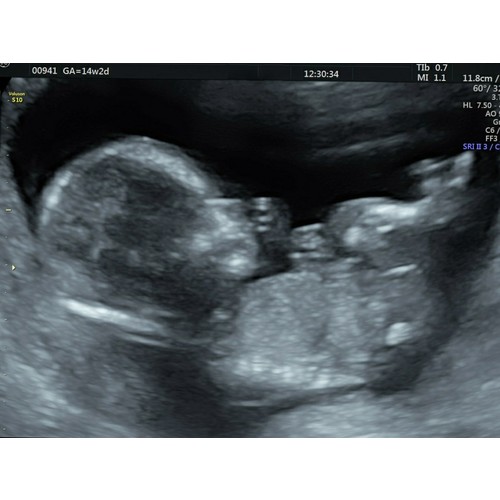

Ik had hem met 16w1d bij ons, wij krijgen een jongen, duurde heel even omdat hij lekker druk was maar toen hij zijn piemel liet zien was het overduidelijk en elke echo laat hij hem weer zien haha 🤦🏼♀️🤦🏼♀️😂😂 ik heb zijn gezicht een keer gezien, zie afbeelding foto maar zijn piemel laat hij elke echo zelfs de groeiechos weer zien haha 😂

Wat een mooie afbeelding 💙💙❤❤